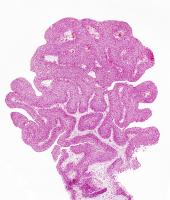

L’étude utilise une nouvelle méthode pour examiner, au niveau moléculaire les cellules nerveuses à la fois dans les tissus sains et dans le cancer du pancréas, chez la souris. Dans les tumeurs du pancréas, les nerfs sont extrêmement bien ramifiés et en contact avec la plupart des cellules tumorales. Grâce à cette analyse moléculaire détaillée des neurones individuels de la tumeur, les chercheurs ont découvert que le cancer du pancréas reprogramme l'activité génétique des nerfs à son propre bénéfice :